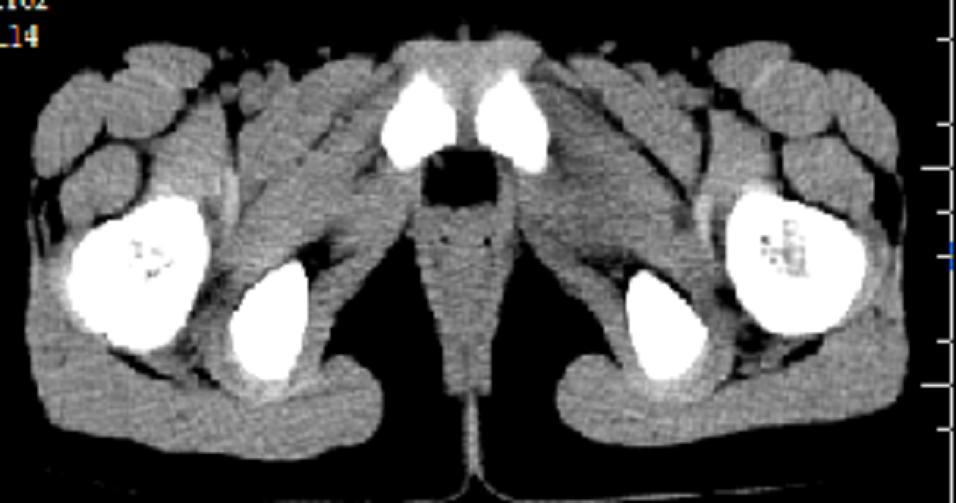

以下是引用zxd95在2008-7-2 10:06:00的发言:[br]左耻骨下支局部骨质破坏,内见小条状小骨片,周围肌间隙模糊,左闭孔内外肌肿胀。[br]儿童患者,首先考虑结核性,以骨质破坏为主(其内小条状小骨片解释为死骨)。[br]鉴别:[br]1、化脓性病变以增生为主;[br]2、肿瘤性病变:良性肿瘤不会有周围软组织的肿胀、模糊;恶性肿瘤病变骨皮质破坏、中断;[br]3、肿瘤样病变:一般也无周围软组织的改变。[br]建议查肺部及结核相关实验室检查。